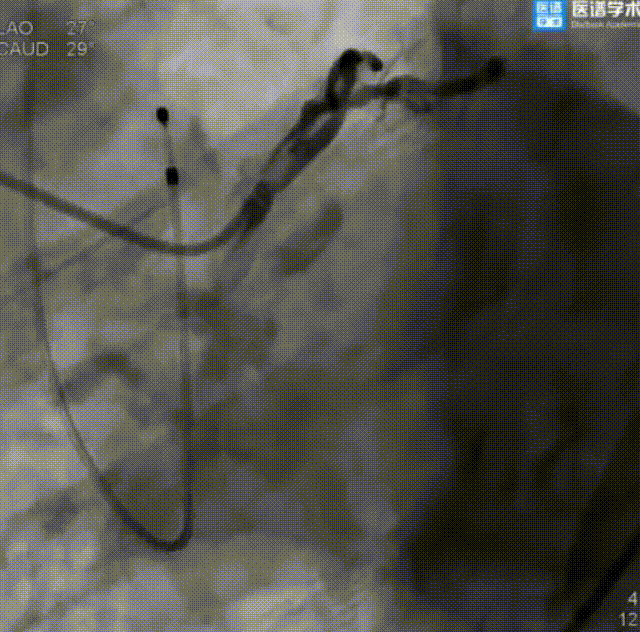

经股静脉二尖瓣球囊扩张成形术:

二尖瓣球囊扩张

PCI术后继续行经股静脉二尖瓣球囊扩张成形术,经右股静脉送入鞘管及导丝穿刺房间隔后,通过导引鞘导入二尖瓣球囊扩张系统,经食道超声确定后,使用21 mm二尖瓣球囊于二尖瓣处进行扩张,术后即刻超声提示跨二尖瓣平均压差4 mmHg,二尖瓣轻度反流。